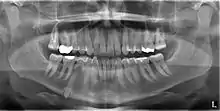

An impacted tooth is one that fails to erupt into the dental arch within the expected developmental window. Because impacted teeth do not erupt, they are retained throughout the individual's lifetime unless extracted or exposed surgically. Teeth may become impacted because of adjacent teeth, dense overlying bone, excessive soft tissue or a genetic abnormality. Most often, the cause of impaction is inadequate arch length and space in which to erupt. That is the total length of the alveolar arch is smaller than the tooth arch (the combined mesiodistal width of each tooth). The wisdom teeth (third molars) are frequently impacted because they are the last teeth to erupt in the oral cavity. Mandibular third molars are more commonly impacted than their maxillary counterparts.

Classifications enable the oral surgeon to determine the difficulty in removal of the impacted tooth.[9] The primary factor determining the difficulty is accessibility, which is determined by adjacent teeth or other structures that impair access or delivery pathway. The majority of classification schemes are based on analysis on a radiograph. The most frequently considered factors are discussed below.

This type of classification is based on the amount of impacted tooth that is covered with the mandibular ramus. It is known as the Pell and Gregory classification, classes 1, 2, and 3.[10]

Relationship of tooth to occlusal plane

The depth of the impacted tooth compared with the adjacent second molar gives the basis for this type of classification. This was also given by Pell and Gregory and is called as Pell and Gregory A, B and C classification. Relationship to occlusal plane Class A-C